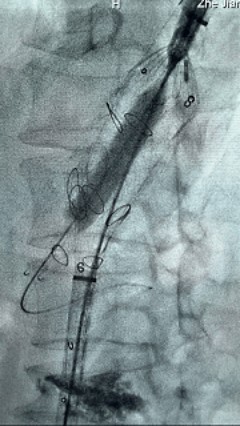

3. 经右股动脉导入超硬导丝,然后导入先健G-Branch 胸腹主动脉主体覆膜支架TAAA3418120e7i1010 一枚,释放主体支架至内分支打开,然后经左侧肱动脉入路,抓捕预置导丝成功后,将长鞘进入内分支出口处。

4. 经长鞘导入导管后,超选入腹腔干动脉,送入先健覆膜支架10*80mm一枚,近端重叠内分支,远端重叠腹腔干动脉,并予以10mm球囊后扩,手推造影显影良好。

5. 撤出腹腔干导丝导管,经左肱动脉长鞘继续抓捕预置导丝将长鞘超选至另一侧内分支,后超选进肠系膜上动脉,沿导丝送入先健覆膜支架10*100mm一枚,近端重叠内分支,远端重叠于肠系膜上动脉,并予以10mm球囊后扩,手推造影显影良好。

6. 解除束径,打开近端后释放,经肱动脉长鞘超选支架外分支,并进一步超选右侧肾动脉,交换加硬导丝,送入覆膜支架6*50mm和7*60mm各一枚,并予以球囊后扩张,手推造影显影良好。

7. 经长鞘重新选入左侧外分支,并超选进左肾动脉,沿导丝送入外周血管覆膜支架7*60mm一枚,并予以球囊后扩张,手推造影显影良好。

8. 从右侧股动脉入路送入腹主支架AB-24-12-110-S,近端重叠胸腹主动脉支架远端,调整好支架位置后释放。

9. 经左股动脉送入导丝导管,超选进腹主动脉支架短腿内,后沿导丝送入髂支,同理,右侧沿导丝送入髂支并释放,使用先健顺应性球囊后扩各支架连接处及支架近远端,最后通过预留导管向瘤腔注入人纤维蛋白粘合剂数支,造影显示分支通畅。